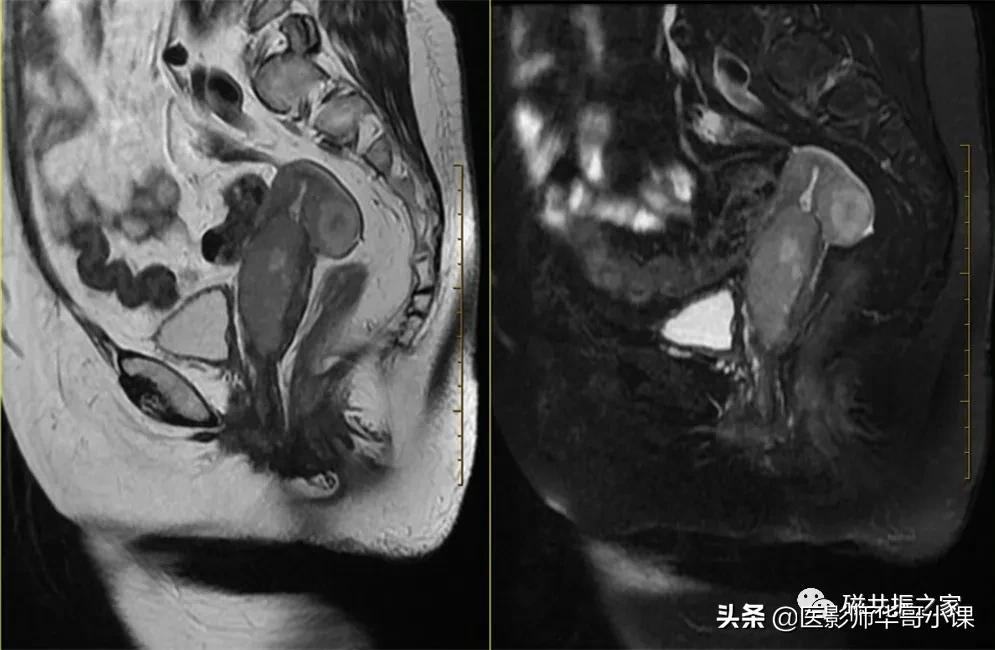

对于前位或后位子宫,如子宫的曲度过大,很多人可能会纠结以子宫为基准定的冠状位相对于人体来说似乎是横轴位;定的横轴位相对于人体来说似乎是冠状位。这一点不必纠结,以子宫为基准定位即可。

矢状位是显示子宫全景较为理想的方位,该序列采用压脂或不压脂均可,但最好能做到小视野的高分辨率扫描。在T2WI上能清楚的显示子宫(绝经前)的四层结构。

2.矢状位是子宫扫描最重要的方位,对于女性盆腔的扫描在大范围的扫描1-2个序列后,应首先扫描矢状位,再扫描小视野的横轴位及冠状位,有利于更准确的定位扫描。

3.由于子宫的形态及位置的差异,应根据子宫不同的形态及位置合理定位扫描,小视野的矢状位和横轴位常采用高分辨率扫描。